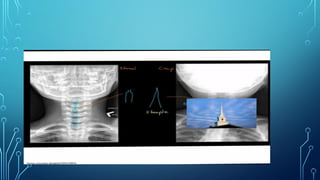

• X-ray Soft tissue Neck lateral- Thumb sign

• Xray neck- AP view – Steeple sign

• Laryngeal examinationis better avoided – red swollen angry epiglottis • X-ray Soft tissue Neck lateral- Thumb sign

• Onset isslow, non toxic • Hoarseness and croupy cough- Barking seal like • Fever low grade • Respiratory difficulties is slow in onset with intercostal and suprasternal recession • Xray neck- AP view – Steeple sign